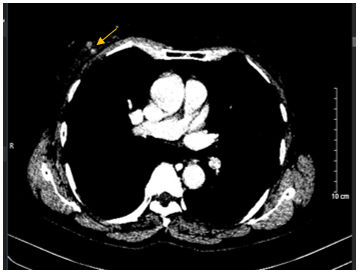

- Cắt lớp vi tính lồng ngực: Không phát hiện tổn thương tổn thương phổi bất thường. Vú phải có nốt ngấm thuốc vị trí 12 giờ-13 giờ, kích thước 10x12mm.

Hình 5: Hình ảnh cắt lớp vi tính lồng ngực: Hình ảnh vú phải có nốt ngấm thuốc vị trí 12 giờ -13 giờ, kích thước 10x12mm (mũi tên màu vàng).

- Cắt lớp vi tính lồng ngực: Không phát hiện tổn thương bất thường. Không còn Nốt ngấm thuốc trước điều trị.

Hình 7:

Hình ảnh so sánh phim chụp cắt lớp vi tính lồng ngực trước điều trị (bên trái) và sau điều trị tân bổ trợ 6 chu kỳ (bên phải). Nốt ngấm thuốc ngực phải trước điều trị (hình tròn màu vàng) đã biến mất hoàn toàn.